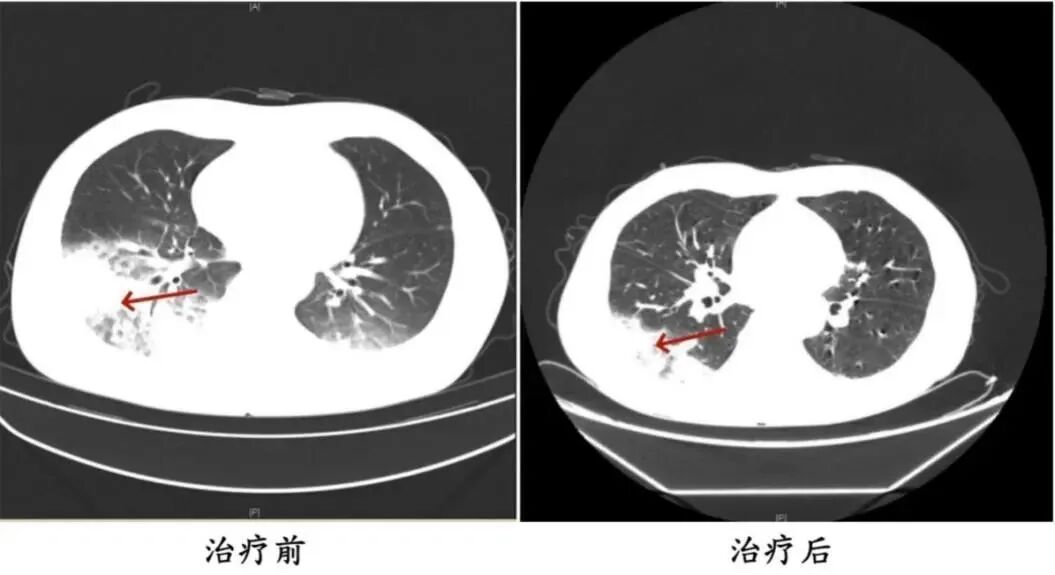

呼吸内科主任沈三英详细询问,并为患者完善了相应检查。结果显示,张先生的左肺竟然“白”了一大片。气管镜检查后,团队再通过肺泡灌洗液NGS检测抓住元凶——军团菌

所幸张先生就医及时,目前体温恢复正常并已顺利出院。